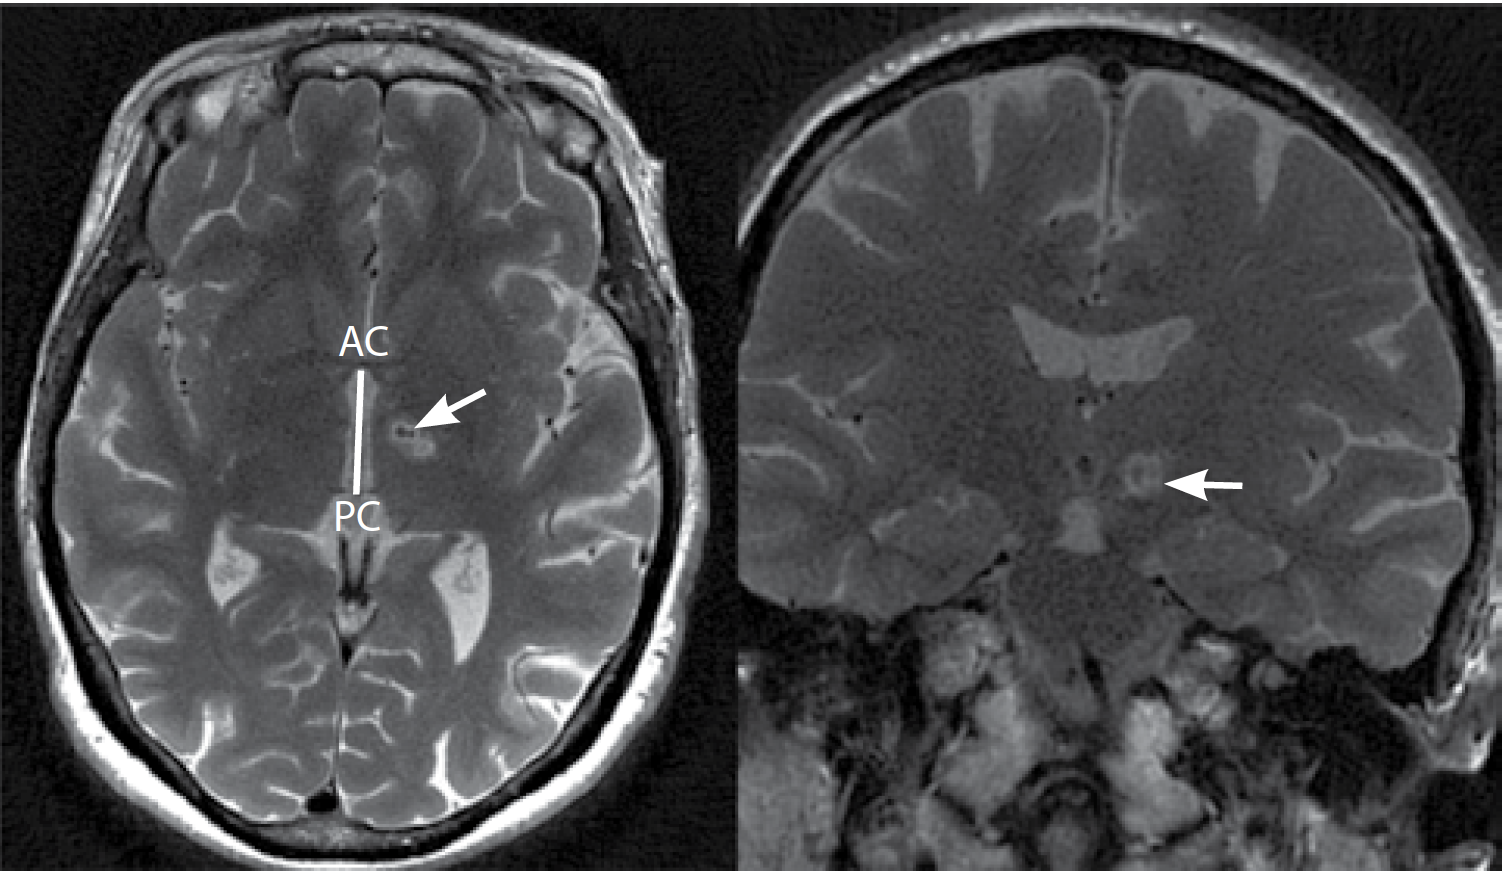

Во время процедуры МР-ФУЗ проводилось контрольное МРТ-исследование головного мозга в режиме T2 в аксиальной, сагиттальной и коронарной проекциях с толщиной среза 2 мм. Интраоперационная визуализация не выявила признаков кровоизлияния или нецелевого нагрева ни у одного из пациентов. После проведения лечения пациентам выполняли контрольное МРТ головного мозга через 2 и 24 ч, 30 дней: определялся незначительный отёк (1–3 мм) по краю и очаги некроза в местах воздействия (рис. 2).

Рис. 2. МРТ пациента через 30 дней после деструкции PTT справа методом МР-ФУЗ в аксиальной и коронарной проекции. Очаг деструкции указан стрелкой.

Fig. 2. Axial and coronal MR images in 30 days after right PTT MRgFUS destruction. The arrow indicates the destruction focus.